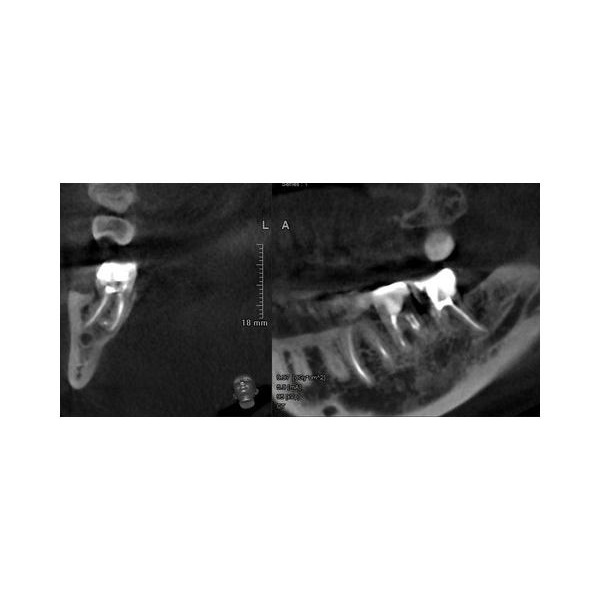

По результатам конусно-лучевой компьютерной томографии (КЛКТ) от 23.10.2022 года, в корневых каналах зуба 4.8 выявили следы пломбировочного материала, не доходящего до верхушки корня. В этой области отмечался овальный очаг разрежения кости с отчётливыми границами размером около 0,5 см в поперечнике.